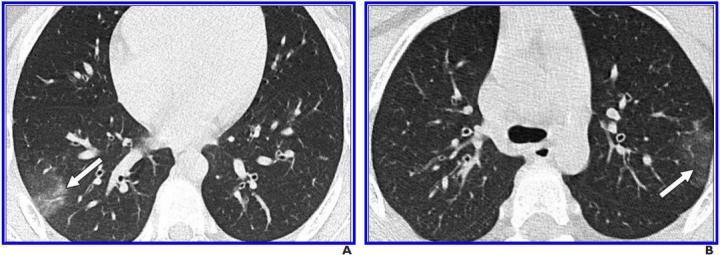

image: A and B, Unenhanced chest CT scans show minimal GGOs (right lower and left upper lobes) (arrows) and no consolidation. Only two lobes were affected, and CT findings were assigned CT severity score of 2.

Leesburg, VA, May 28, 2020--An investigation published open-access in the American Journal of Roentgenology (AJR) revealed a high frequency of negative chest CT findings among pediatric patients with laboratory-confirmed coronavirus disease (COVID-19), while also suggesting that bilateral, lower lobe-predominant ground-glass opacities (GGOs) are common in the subset of patients with positive CT findings.

"CT findings were often negative (77%)," Steinberger et al. concluded, adding that positive CT findings seen in children included GGOs with peripheral lung distribution, crazy paving pattern, as well as the halo and reverse halo signs.